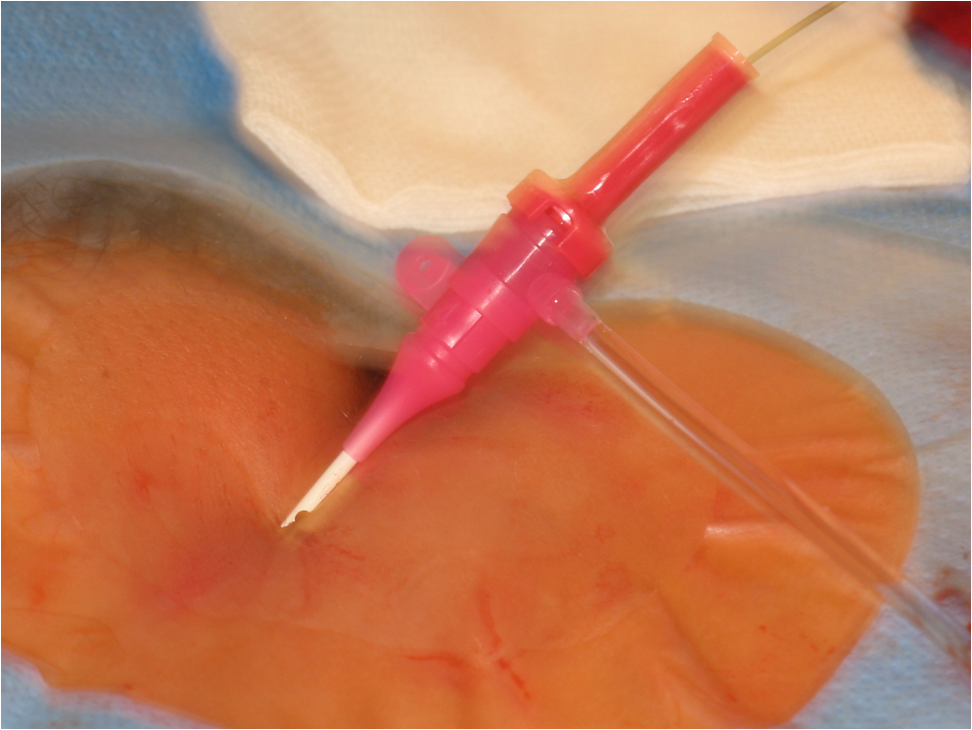

Seldinger technique is used for vascular access. Arterial puncture by a Seldinger needle (Fig 1, Upper row, left panel) is most often pulse-directed (by palpation), but can be accessed by ultrasound guidance. Most commonly used access sites are common femoral and brachial arteries, radial arteries are used mostly by cardiologists, popliteal artery can be rarely punctured in special cases (retrograde recanalisation of superficial femoral artery occlusion). A guidewire is inserted into the needle (Fig 1, Upper row, right panel), the needle is withdrawn (Lower row - left panel) (at this point the puncture site should be compressed to prevent bleeding); a few mm dissection may be done by a scalpel, the introducer sheath and then a catheter is fed onto the guidewire (Lower row - right panel); then the guidewire can be withdrawn and contrast medium can be inserted through the catheter. More information on contrast medium is available in chapter 7.